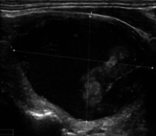

Figure 6 illustrates the segmentation outcomes attained with different neural networks using the same dataset. The enhanced U-Net network proposed in this study is evaluated alongside expert gold standards, Swin-Unet, U-Net, and other well-known network models. The segmentation results from the Swin-Unet network show jagged edges and less smooth nodule edge segmentation, leading to suboptimal outcomes. In the case of U-Net, there are evident under-segmentations with significant discrepancies in the segmented area of some nodules, resulting in inaccurate segmentation results. However, the use of the improved U-Net network introduced in this research produces smoother edges of the segmented thyroid nodules, and the edge contours more closely align with those of the expert gold standard. Moreover, the errors in shape and segmented area are smaller compared to those seen with U-Net and Swin-Unet. The findings suggest that the improved U-Net network provides superior performance in thyroid nodule segmentation.

(a) Original image

(b) Expert gold standard

Figure 6. Ultrasound image segmentation results of thyroid nodules using different networks